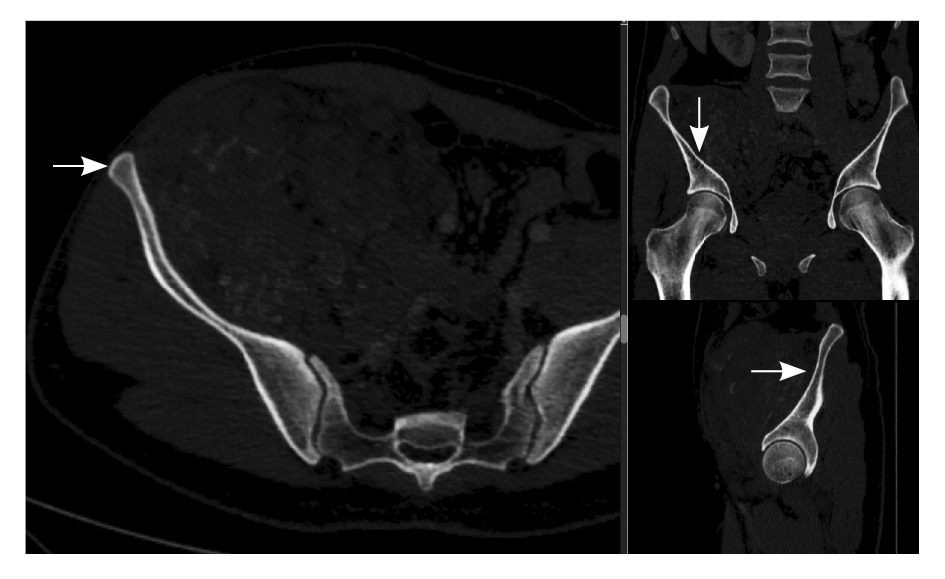

Рис. 2. Мультиспиральная компьютерная томография органов брюшной полости и забрюшинного пространства, режим костного окна. Кортикальный слой правой подвздошной кости прослеживается равномерно на всем протяжении, без признаков деструкции (стрелки)

Близкое расположение внутримышечных гемангиом к костям приводит к контактным изменениям последних. Методами лучевой диагностики выделяют три типа изменений костных структур – периостальные, кортикальные и медуллярные. Близость расположения образования к кости статически значимо коррелирует с любым типом костной реакции, а размер образования – лишь с медуллярным [14]. Агрессивный тип периостальной реакции и деструкция кортикального слоя могут быть ошибочно приняты за первичную опухоль кости [6, 15]. Однако эти изменения факультативны: так, в нашем исследовании никаких изменений костных структур отмечено не было.